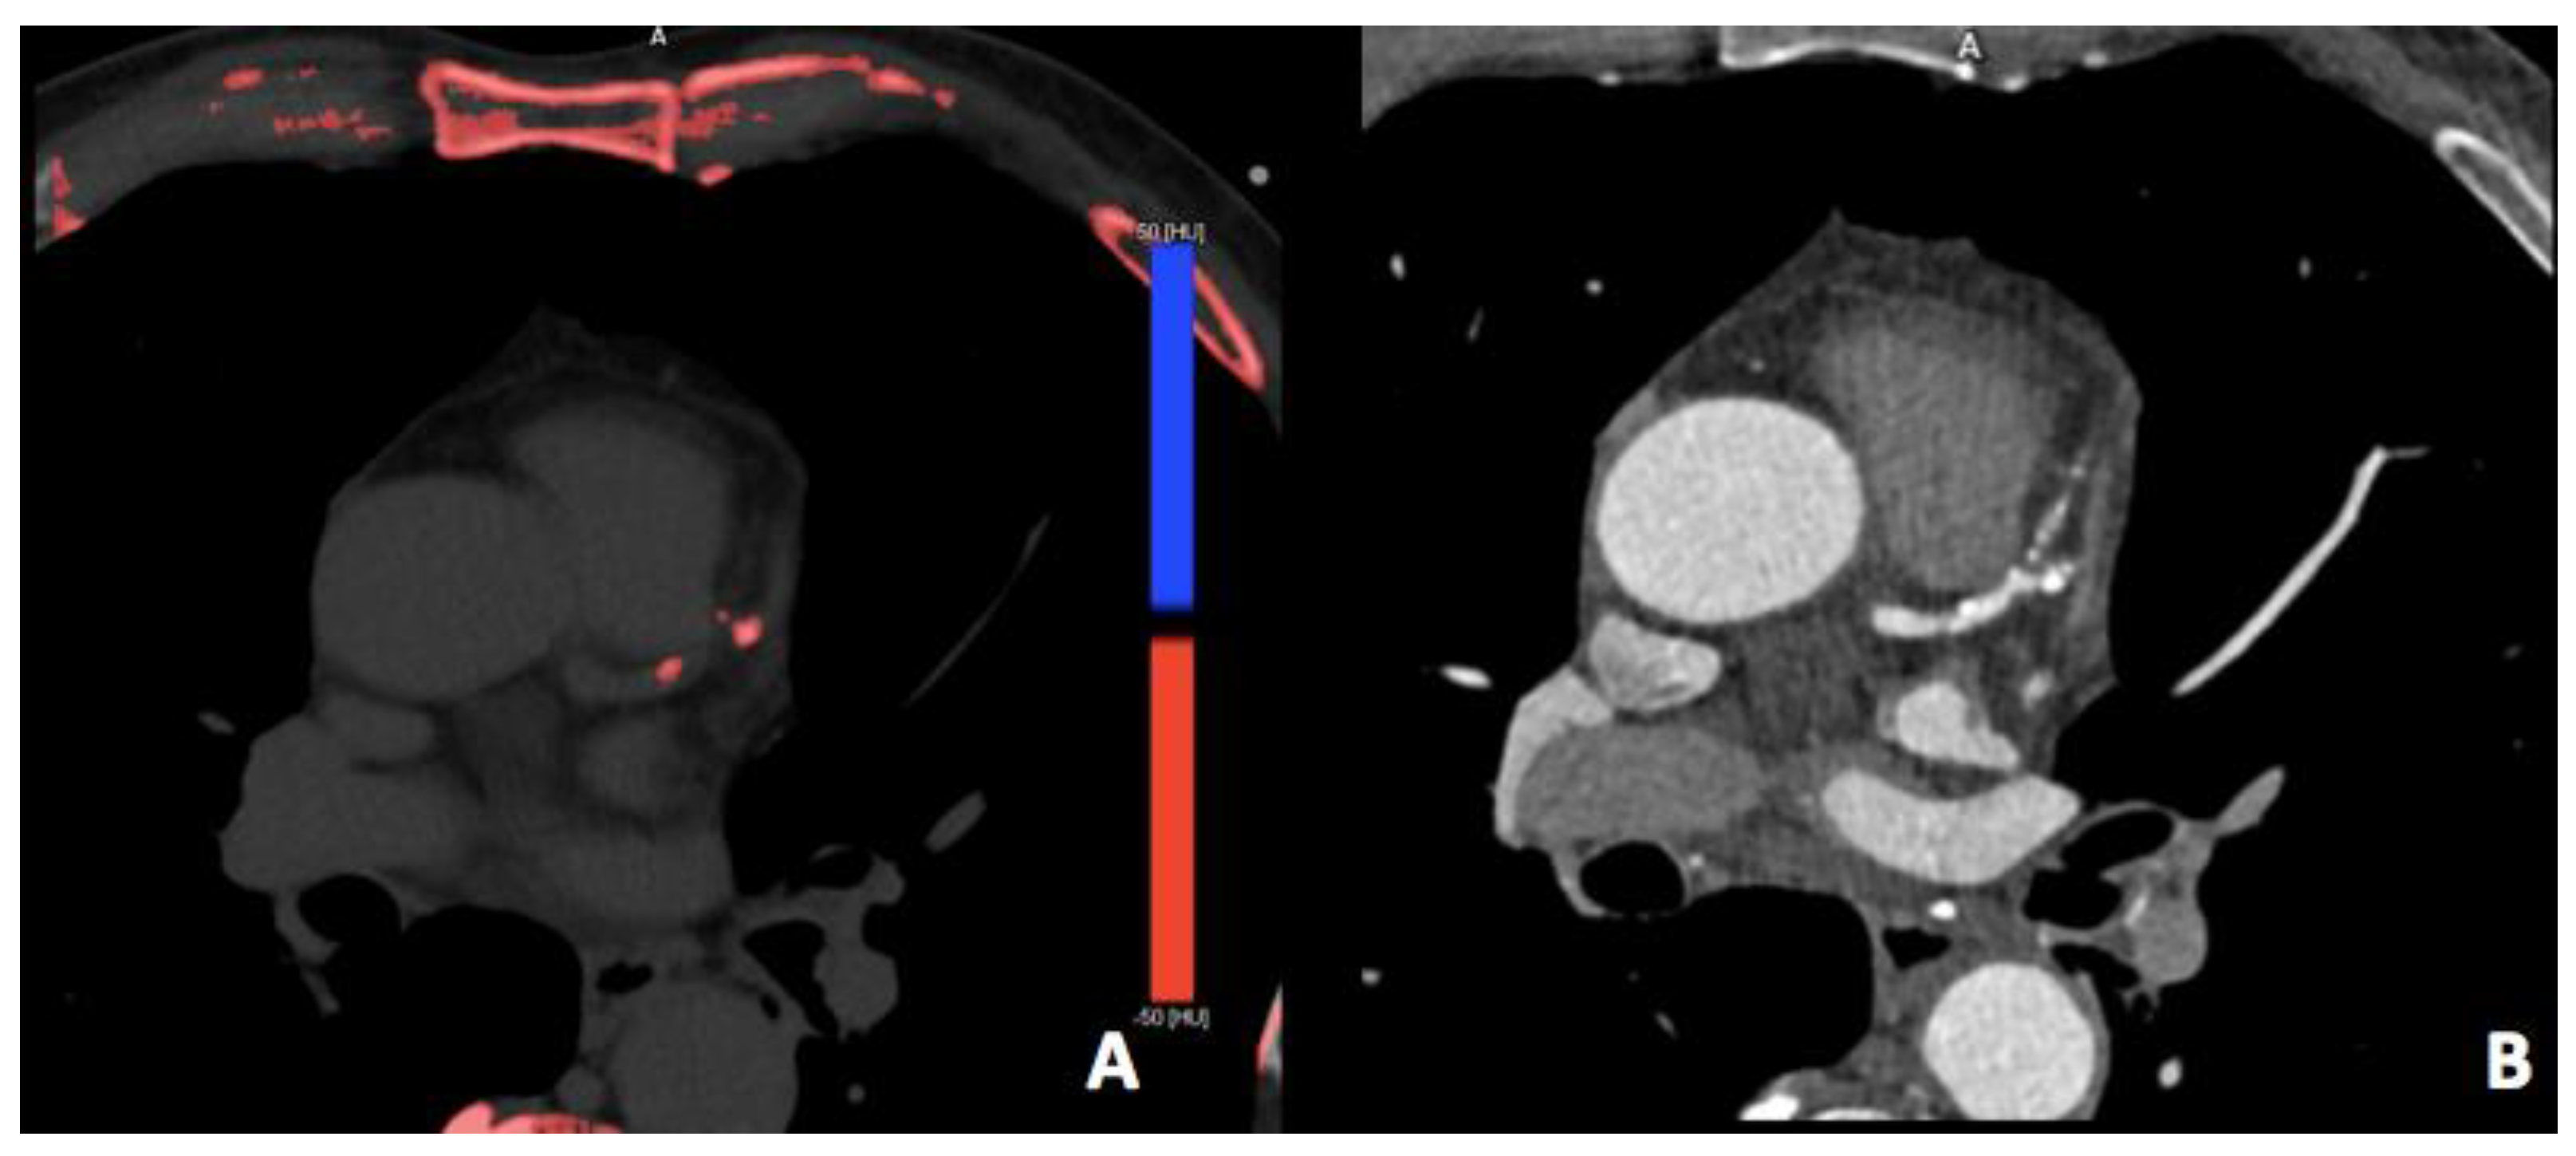

3.2. Virtual Non-Contrast Imaging